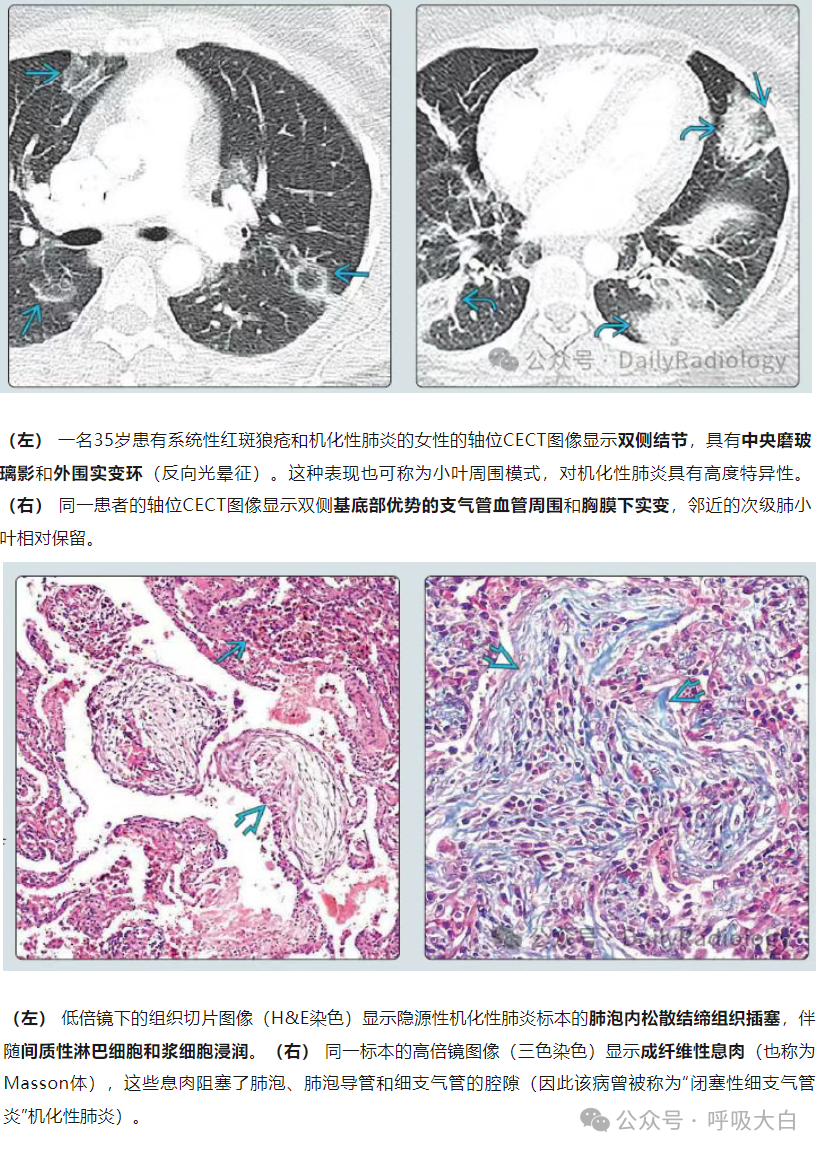

COP肺部CT表现多数为肺泡实变影,可从2cm至双侧广泛病变,病灶多位于胸膜下或肺野外带。病灶呈不规则斑片状,累及多个肺段。部分患者同时可见网状影、不规则线状影和结节影。网格状阴影较少见,很少有胸腔积液等胸膜渗出征象。

⑤多双肺受累:两侧中下肺分布为主,占88%;沿着胸膜分布占96%,不累及胸膜占40%。

COP患者肺活检标本的组织病理学结果显示腔内有疏松结缔组织栓子,累及肺泡腔和肺泡管,也可累及细支气管,肺的基础结构保留。腔内疏松结缔组织栓子常以细柄连接到肺泡壁,并通过肺泡孔从一个肺泡延伸到相邻的肺泡,形成特征性的蝴蝶状结构。肺泡壁可出现轻度慢性炎症(如涉及淋巴细胞和浆细胞)。

COP的主要病理变化是肺泡内、肺泡管、呼吸性细支气管及终末细支气管内有息肉状肉芽组织增生,形成Masson小体,其病变表现单一,时相一致,呈斑片状和支气管周围分布,位于气腔内,含极少炎性细胞,肺结构往往正常。肺泡腔内肉芽组织呈芽生状,由疏松的结缔组织将成纤维细胞包埋而构成,可通过肺泡孔从一个肺泡扩展到邻近的肺泡,形成典型的“蝴蝶影”。肉芽组织中可存在炎性细胞,尤其在疾病早期,可见单核细胞、巨噬细胞及少量的肥大细胞、嗜酸粒细胞、中性粒细胞。在空的肺泡腔内可见肺泡巨噬细胞,部分肺泡巨噬细胞呈泡沫状,伴有Ⅱ型肺泡上皮细胞增生。受累的肺泡间隔有少量淋巴细胞和浆细胞浸润为主的轻度炎性渗出,肺泡间隔稍增厚。